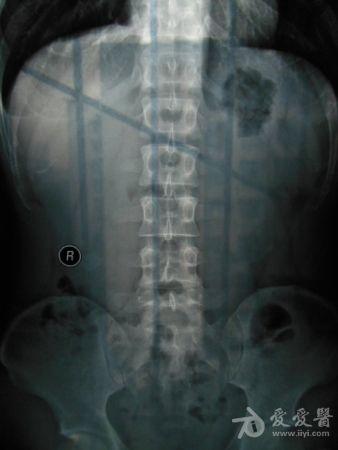

请老师看看这个腰椎和盆骨的平片有无问题

摔了一跤右臀着地,同时闪到腰,查出有椎间盘突出,目前是右臀麻木,整个右腿酸胀沉重。肌力正常走路正常,坐不到5分钟右腿就酸胀难忍。明显觉得左右**感觉不一样,右边软得多,

自觉下腰和盆骨感觉别捏,有歪斜感,扭腰时觉得舒服。腰4右侧一下有异物感。今天照了个腰椎正侧位和盆骨的正位平片,医生说没什么问题,拿来请各位老师看看腰椎和盆骨有没有错位,旋转,不等高等情况,再次感谢。

照该片看应该是骨盆旋移

这种症状拍平片没有什么意义,选择MRI或者CT吧

看片子没发现什么大的问题,没有骨折,没有增生。腰椎间盘突出做核磁共振最清楚。